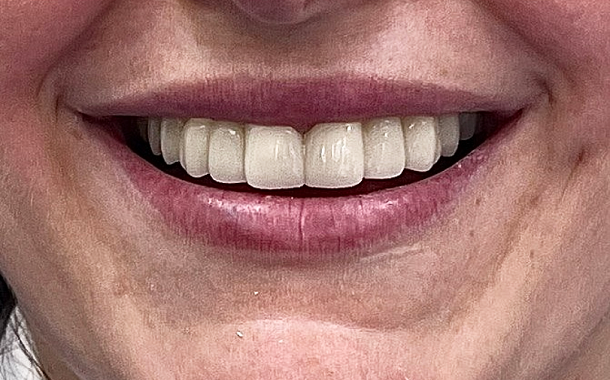

Возвращение эстетики улыбк.

Если имплантация проводится в районе передних зубов -

Мгновенное восстановление жевательной функции

Благодаря временным коронкам высота прикуса и работа сустава остаются правильными с первого дня начала имплантации. Постоянные коронки фиксируются только спустя 4–6 месяцев, когда зубной имплант полностью прижился.